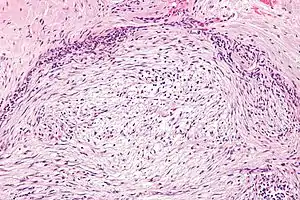

| Micrograph of nodular fasciitis showing the haphazard arrangement of cells (tissue culture-like pattern). H&E stain. | |

The microscopic histopathology of hematoxylin and eosin stained nodular fasciitis tumors (see above and three below figures) consists of spindle-shaped myofibroblastic cells (i.e. cells with features of smooth muscle cells and fibroblasts.).[8] These cells are in a myxoid (i.e. more blue or purple compared to normal connective tissue because of excessive uptake of the hematoxylin stain) or a collagenous (high content of collagen fibers) tissue background. The neoplastic myofibroblasts are arranged in whorls and/or short bundles. These cells may show high rates of replicating as judged by their mitotic index but these mitoses are normal in appearance. The tumor tissues often contain red blood cells, lymphocytes and giant osteoclast-like giant cells and may contain sites of bone-like tissue.[10] NF is sometimes classified into three subtypes based on its predominant histopathological pattern: myxoid or reactive (type I), cellular (type II), and fibrous (type III).[4] These patterns appear related to the duration of the lesion with the myxoid variant tending to have the shortest duration and the cellular and fibrous variants tending to have progressively longer durations.[14]Immunohistochemical analyses indicate that the cells in NF usually express smooth muscle actin, muscle specific actin, and vimentin proteins but generally do not express CD34, S-100 protein, desmin, trypsin, factor VIII, F4/80 (also termed macrophage-specific antigen), or HLA-DR1 proteins.[10] Uncommonly, the cells in NF tumors also express the CD68 (a histiocyte-specific marker) protein.[4]